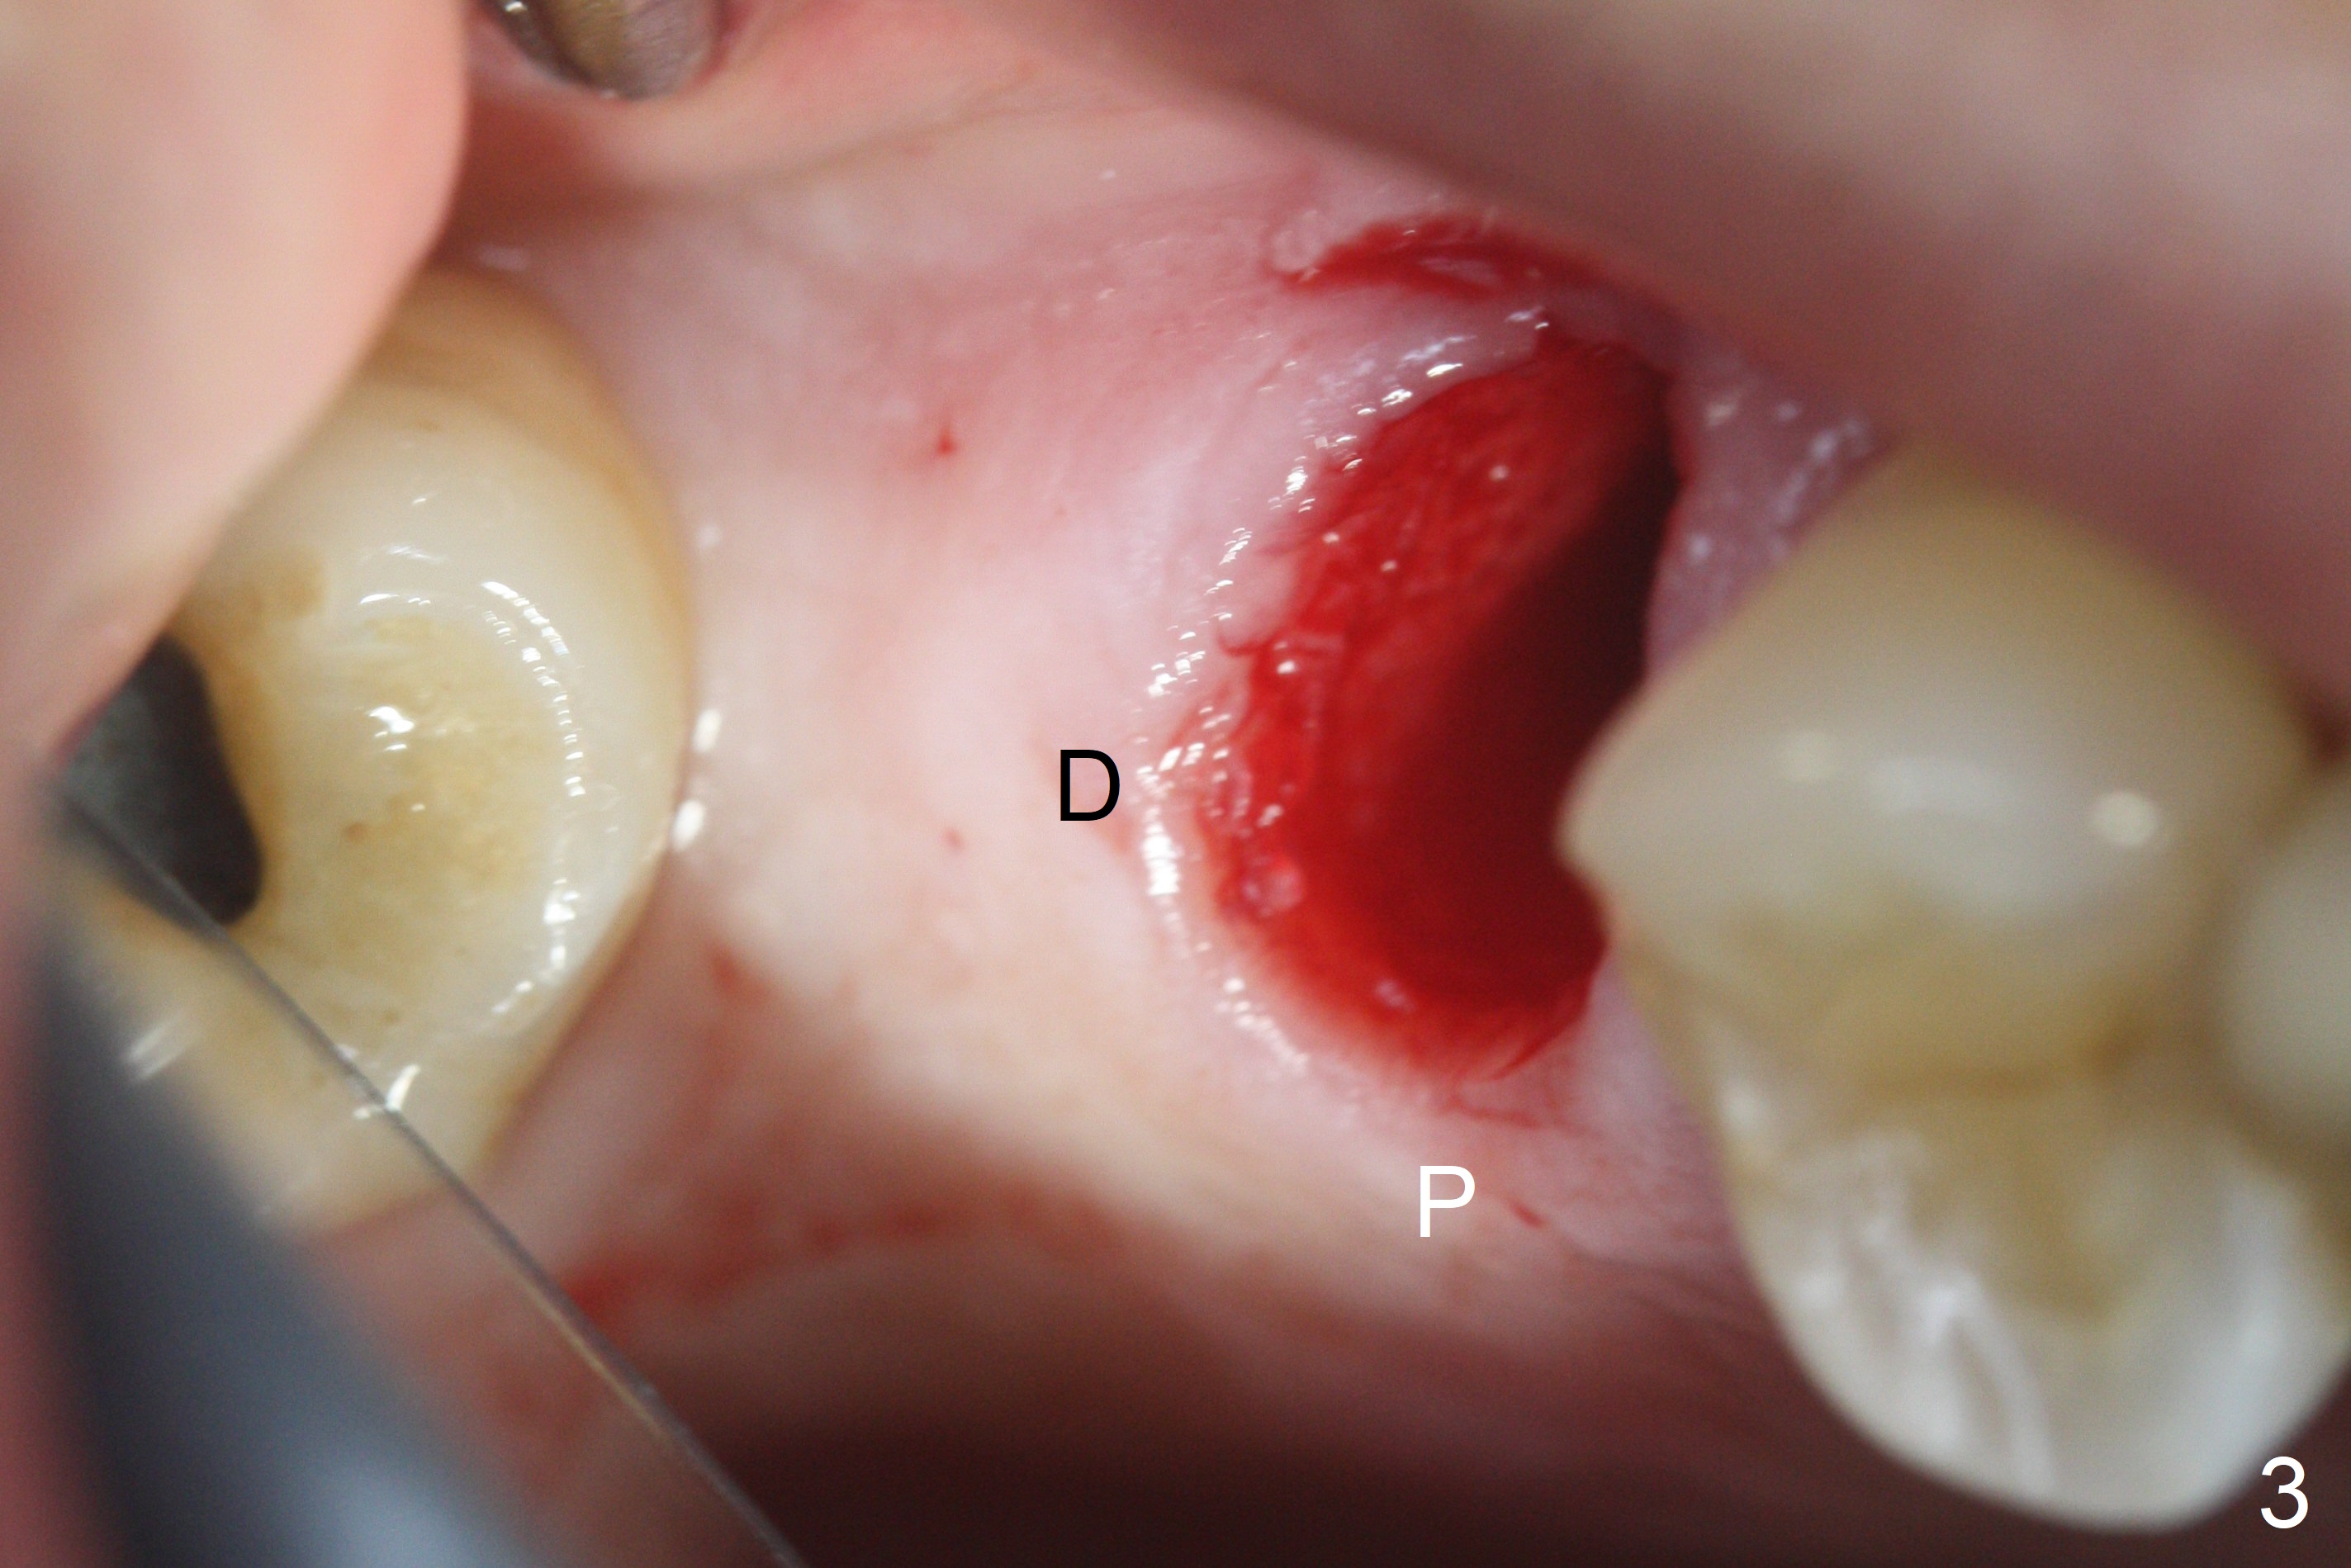

The palatal cusp of the affected 2nd premolar is apparently rotated distal (Fig.1). It is more obvious for the socket (Fig.2): the palatal (P) portion of the socket is more distal than the buccal (B) one. When the gauze is removed (Fig.3), Lindamann bur is used to remove the disto(D)palatal bone of the socket (data not shown), followed by starter drill in the DP wall obliquely (Fig.3'). Once the drill enters the bone for 1-2 mm, the bur is straightened and pushed slightly distal (Fig.3''). Fig.4 shows a parallel pin distal (overcorrect) to the original socket (Fig.4 red dashed line). Sequential osteotomy is conducted until 3.8x13 mm drill for 18 mm (Fig.5): note the 2 steps of the osteotomy (red lines). Since the apical portion of the osteotomy is larger than the drill, a larger implant than expected (5x16 mm) is placed. The implant ends up in the middle of the edentulous area (due to the stepped osteotomy; Fig.6-9; >60 Ncm). Vera allograft is placed (Fig.7-9 *) prior to and after placement of a 6.5x4(3) mm abutment (Fig.8-10). The remaining socket opening is sealed with a piece of Collagen plug (Fig.10 *). The socket is then closed by an immediate provisional (Fig.11 P). The abutment is retightened 2 months postop (Fig.12,13). The crown is cemented 4.5 months postop. Panoramic X-ray and CT are taken nearly 7 months post cementation (Fig.14,15) when the patient is ready for #30 implant guide preparation.